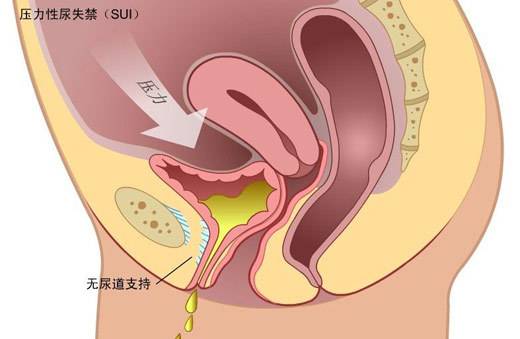

A:女性陰道壁囊腫是一種良性病變,可以單發也可以多發。如果囊腫小,位置低,可以在門診用利普刀進行造口手術,也可以住院做陰道壁囊腫的剝除手術,手術當中應該注意周圍的解剖結構,避免損傷尿道和膀胱。囊腫體積大,位置深,比如位於陰道後穹窿,部分囊壁可能……

A:腫瘤原發於陰道的稱為陰道癌症,確診需要組織學病理檢查。主要包括鱗狀細胞癌、腺癌,其他如罕見的惡性黑色素瘤、肉瘤等。主要的臨床表現為絕經後後子宮出血,同房後出血或陰道不規則出血,合併感染時陰道分泌物有臭味。陰道癌的治療以手術治療為主,放療化療……

A:陰道癌如果是在早期,只是局部病灶出現,沒有發生血液和淋巴轉移的情況下,可以進行手術切除,術後再輔助化療放療等方式治療,能夠達到很好的治療效果。如果已經出現了外陰或者是宮頸等其他部位的轉移的話,這個時候做手術不能全部切除了,可選擇放化療治療,……

A:陰道癌患者的治療應遵循個體化原則,依據患者的年齡、疾病分期、病灶部位確定治療方案,採用放射治療或手術治療。由於發病率低,患者應集中於有經驗的腫瘤中心治療,總體陰道上段癌可參照宮頸癌的治療,陰道下段癌可參考外陰癌的治療。一、藥物治療陰道癌……